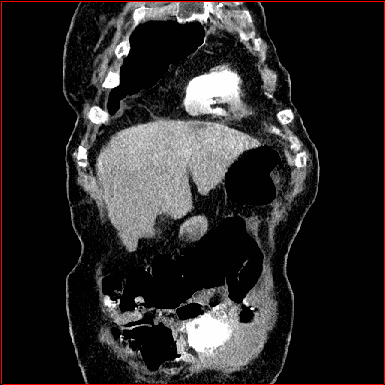

MAISI-v2 Controlnet qualitative Results:

Figure 5 shows qualitative results for MAISI-v2 Controlnet on 5 types of tumors.

Lung Tumor

0.75×0.75×0.60.75\times 0.75\times 0.6

mm

512×512×512512\times 512\times 512

Liver Tumor

0.75×0.75×0.50.75\times 0.75\times 0.5

512×512×768512\times 512\times 768

Panc. Tumor

1×1×11\times 1\times 1

Colon Tumor

0.75×0.75×1.50.75\times 0.75\times 1.5

512×512×256512\times 512\times 256

Bone-Les

1×1×1.31\times 1\times 1.3

512×512×384512\times 512\times 384

Figure 5: MAISI-v2 segmentation-guided results for five types of tumors. We show results for different voxel spacing and volume size to demonstrate the flexibility of MAISI-v2. Different Hounsfield Unit window is used to better show the contrast between tumor and normal tissues.